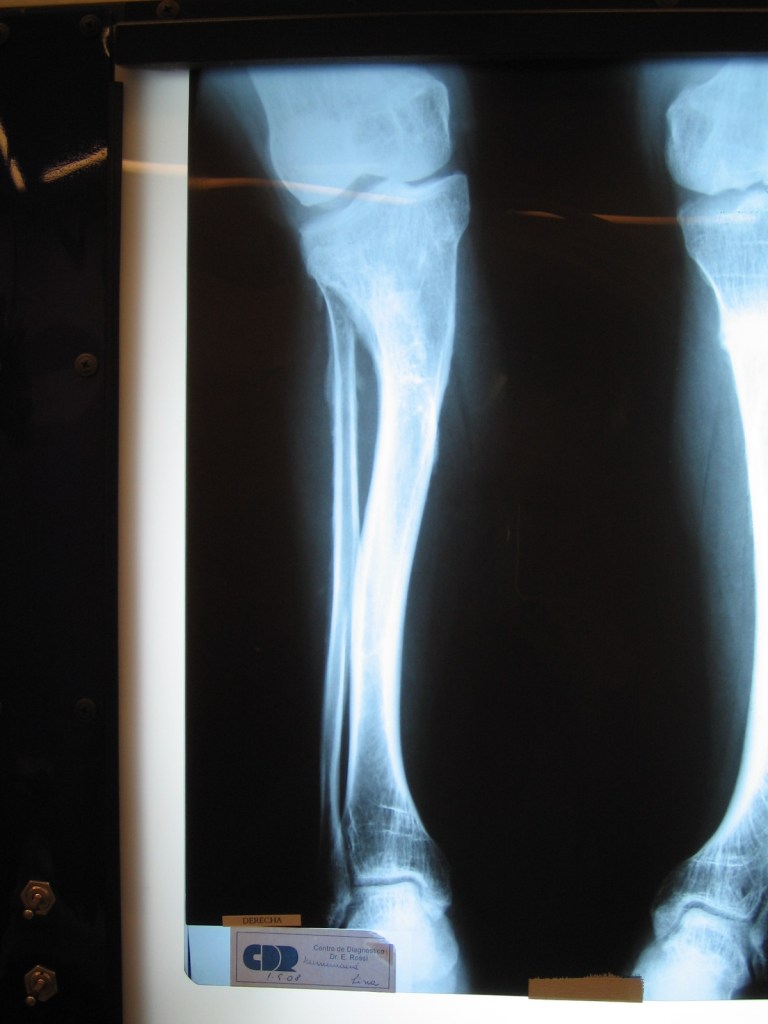

Arrieta

Mensaje de Agradecimiento

Tras varios años de soportar dolores que me impedían caminar y sin ninguna opción de tratamiento mi hueso en el pie me produjo una infección ósea la cual mi única opción en mi provincia era la amputación

Luego de consultar en Cotram no solo me ofrecieron tratar la infección sino corregir mi pie y devolver el largo de la pierna

Al final de 6 meses puedo caminar y no tengo más dolores